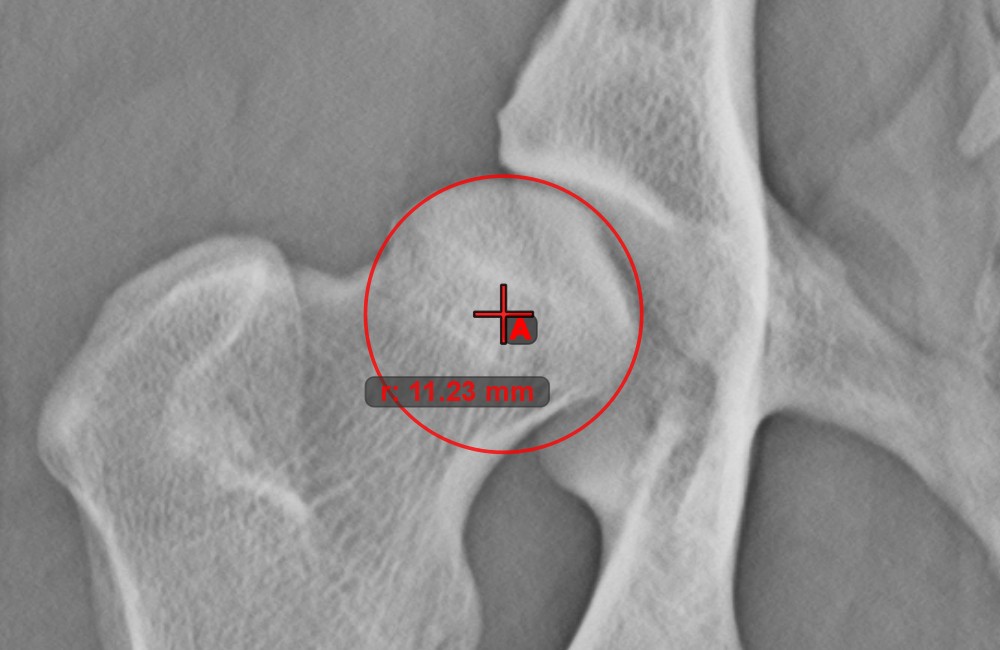

Circle from 3 Points

../_images/image69.jpg

The Circle from 3 Points tool is a simple and effective way to create a circle from just three points.

Start by selecting the tool from the left toolbar and assign it to one of the available mouse buttons. Place the three points of the circle, or select the points from ones available on the scene. The circle will be automatically created based on the position of the three points. The origo of the circle will always be marked with O. The radius of the circle is automatically calculated.

Modify the position of the three points to change the radius of the circle by using the Select/Move Item tool.

../_images/image108.jpg